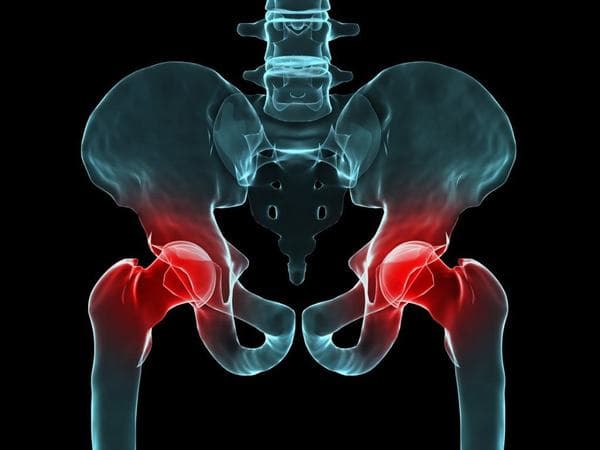

Chữa trị đau khớp háng hiệu quả NHANH không cần phẫu thuật

Đau khớp háng khiến nhiều người gặp khó khăn trong vận động, đi lại, sinh hoạt. Vậy chữa trị đau khớp háng thế nào hiệu quả được rất nhiều người bệnh quan tâm, tìm hiểu. Đau khớp háng do nhiều nguyên nhân khác nhau gây ra. Vì thế để có cách chữa trị đau khớp […]

Điều trị trật khớp háng bẩm sinh ở trẻ em cần làm sớm

Trật khớp háng bẩm sinh là tình trạng chỏm xương đùi của một hoặc cả hai bên khớp háng bị trật ra khỏi vị trí bình thường của khớp háng. Hiện nay chưa có cách nào để phòng ngừa dị tật trật khớp háng bẩm sinh. Vì vậy, việc phát hiện sớm có vai trò […]